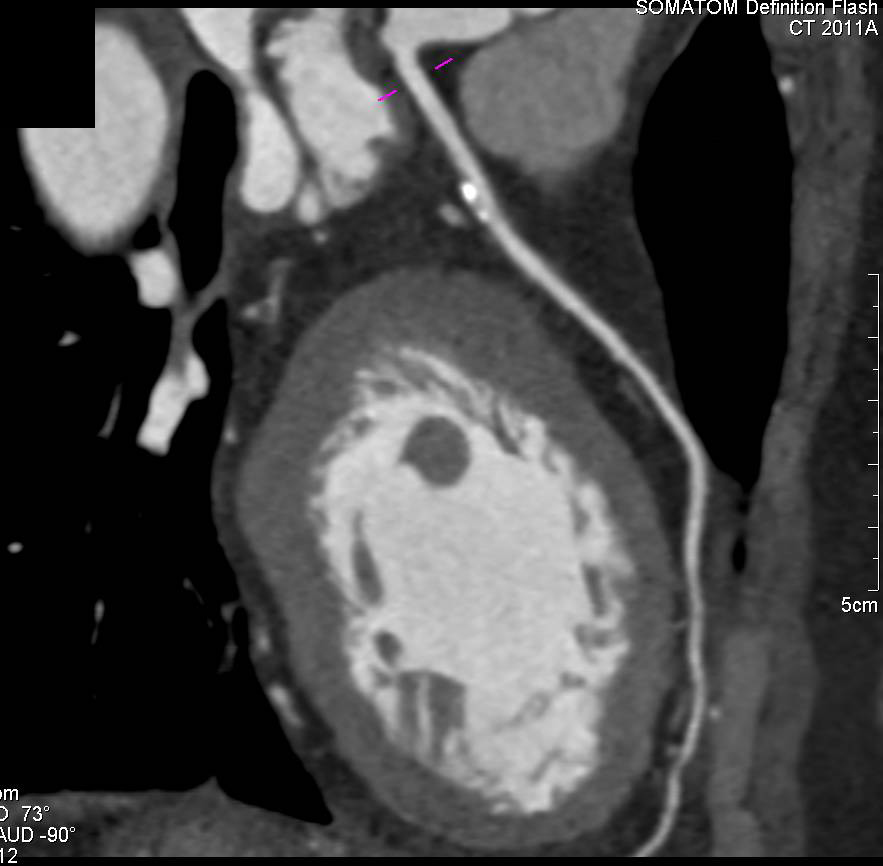

CCTA: Calcified Plaque Left Anterior Descending Coronary Artery (LAD)